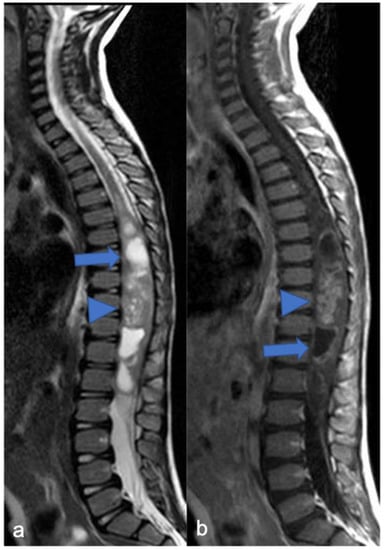

3. Ependymomas